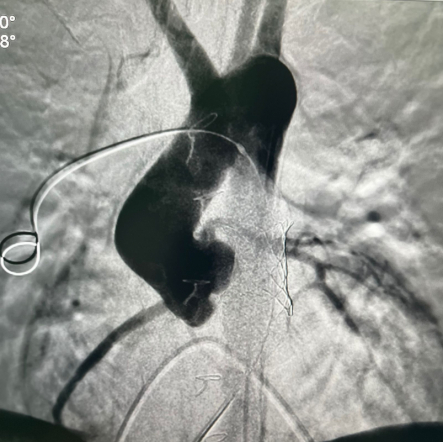

У пациента из Луганской Народной Республики просвет ранее имплантированного кондуита составлял 1,5 сантиметра, поэтому рентгенхирурги на первом этапе расширили его методом баллонной дилатации. При этом был риск разрыва сосуда, поэтому, чтобы избежать возможных осложнений, медики сначала имплантировали стентграфт – металлический каркас, покрытый герметичным полимером. Просвет кондуита удалось расширить до необходимого диаметра. Затем через бедренную вену хирурги доставили к сердцу искусственный биологический клапан лёгочной артерии Myval индийского производства.

Сложную операцию провела команда врачей Педиатрического университета - рентгенэндоваскулярные хирурги Михаил Комиссаров, Владимир Приворотский и Иван Алешин. Неоценимую помощь медикам СПбГПМУ оказал заведующий отделением рентгенэндоваскулярных методов диагностики и лечения  Городской многопрофильной больницы №2 Евгений Шлойдо.